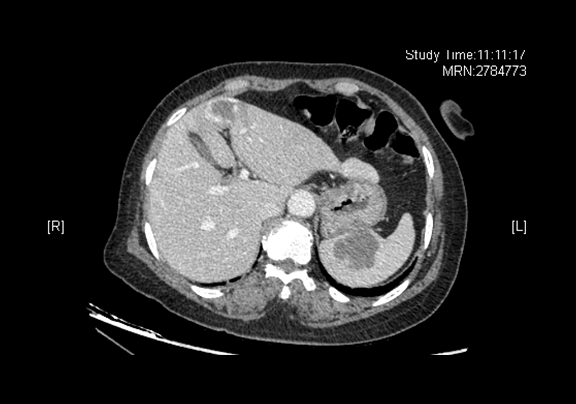

辅助检查:2015-12-07

全腹CT 肝左叶内略低密度灶,脾脏内略低密度灶

术前CT检查:

动脉期

静脉期

平衡期